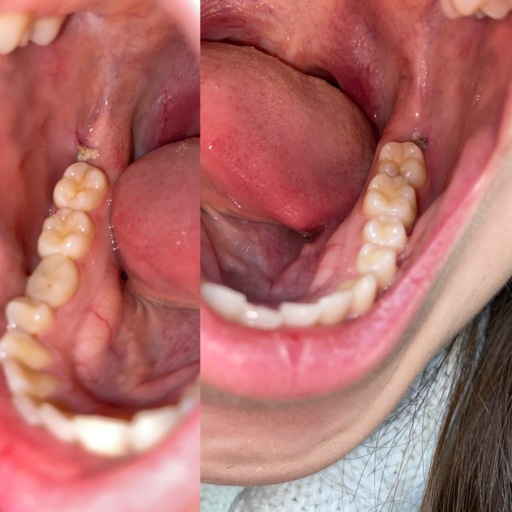

Cutting a frenulum between upper and lower gums

Hi, I have a frenulum on the right side of my mouth. It connects to my gums about 1cm behind the upper and lower back molars. It has become tight and painful. Have you ever seen anything like this? Is it safe to have it cut? I will attempt to add a photo. Thank you, H. Jay Graber

A frenum or frenulum is a small fold of tissue that restricts and secures the motion of a mobile organ. I have not heard of a frenulum in the back of the mouth. It would be best to bring this to the attention of your dentist, especially because it is causing discomfort. I did not see a picture attached to your question, however I am wondering if it is part of your cheek or possibly an impacted tooth that may be causing this discomfort. Use warm salt water rinses several times a day to soothe the tissues until you have a proper exam and diagnosis.

A frenulum or frenum is a small fold of tissue that restricts or secures the motion of a mobile organ. I have not seen a fold of tissue (unless sutured) that connects distal to the molars. There is a frenum that connects your tongue to the floor of your mouth as well as one that attaches your lips to your jaws. Since you are experiencing pain, it is important for you to see your dentist immediately to be sure you do not have an infection or a tooth that is creating swelling in the area.